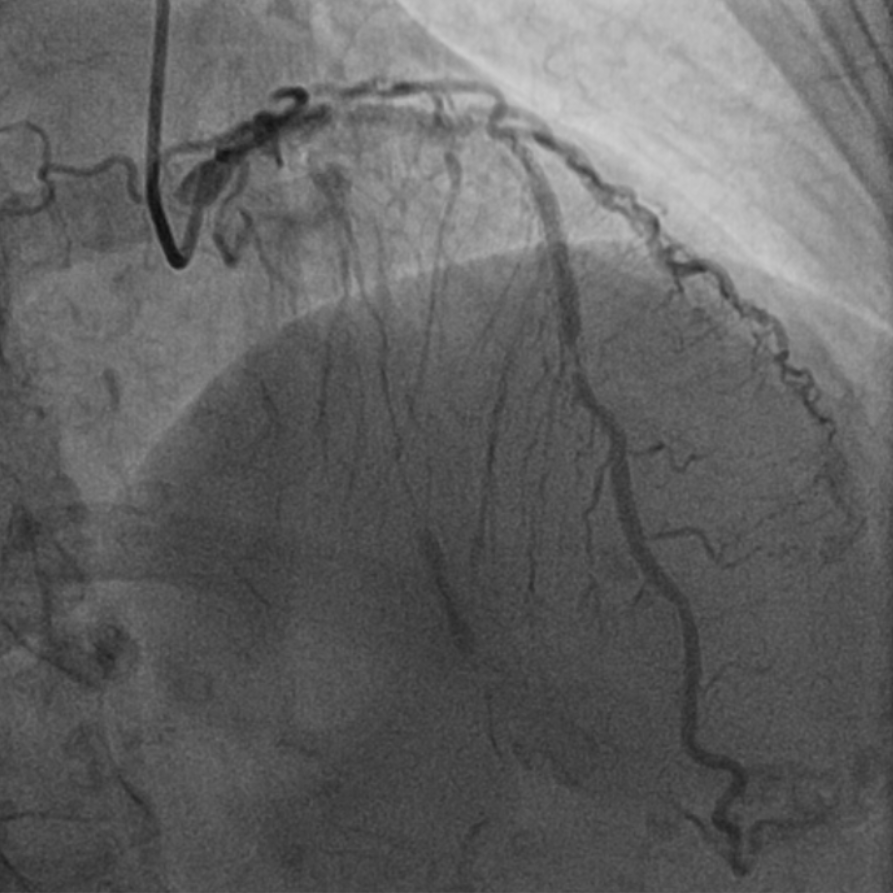

图1 外院手术过程,RCA无法扩张

该患者为68岁女性,14年前于当地医院接受冠脉介入治疗,于左主干至前降支、回旋支及右冠状动脉共植入5枚支架,近10天来再次出现劳力性胸痛,于当地医院造影提示右冠中段支架及左主干支架内再狭窄,回旋支支架内闭塞,由于家属拒绝行CABG治疗,当地医院尝试处理右冠支架再狭窄时球囊未能扩张,为求进一步诊治遂转入西安交通大学第一附属医院心血管内科进一步诊治。